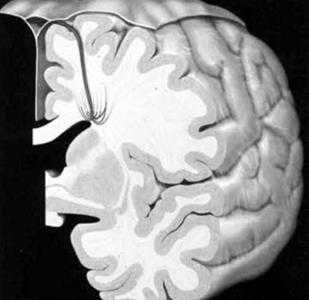

Венозная мальформация. Схема. Определяются мелкие расширенные венулы в виде «зонтика», «головы медузы», дренирующиеся в крупную транскортикальную вену, которая, в свою очередь впадает в верхний сагиттальный синус.